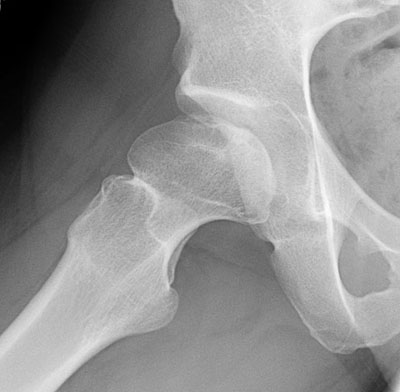

Legg-Calve-Perthes_Disease (4).jpg

العلاج :

- في حالة زيادة نسبة نخر العظم أو تكون التشوهات بعظمتي الورك فان الجراحة هي السبيل الوحيد للعلاج.

المضاعفات:

- مرض بيرثيز قد يسبب تشوهات رأس عظمة الفخذ وبالتالي قصر الطرف السفلي بسبب انضغاط رأس عظمة الفخذ وبعد فترة زمنية تتكون زوائد عظمية وتأكل الغضروف بالحرقفة .

العلاج الجراحي :

- VARUS DEROTATION OSTEOTOMY

-,,,,FING PROCEDURES

-TRANSCERVICAL DRILLING AND BONE GRAFTING

-PELVIC OSTEOTOMY

-CHEILECTOMY

-LATERIZATION OF GREATER TROCHANTER